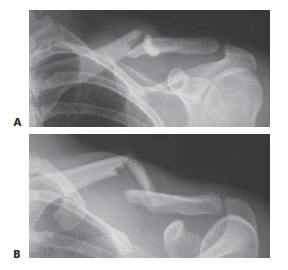

Meticulous preoperative planning is the cornerstone of successful intramedullary clavicle fixation. The diagnostic workup begins with a comprehensive physical examination. On visual inspection, the surgeon will frequently observe notable swelling, ecchymosis, and a gross deformity characterized by the affected shoulder drooping downward, forward, and medialward. The skin must be meticulously inspected for tenting, abrasions, or the classic transverse ecchymosis indicative of a seatbelt shoulder strap injury. Gentle palpation will reveal point tenderness and crepitus. Crucially, the degree of clinical shortening must be quantified by measuring the linear distance from the sternal notch to the acromioclavicular joint bilaterally and calculating the deficit. A rigorous neurovascular examination is mandatory to rule out brachial plexus traction injuries or subclavian vessel compromise.

Radiographic evaluation requires a minimum of two high-quality orthogonal projections. A standard anteroposterior (AP) view is often obscured by the overlapping ribs and thoracic anatomy. Therefore, a 45-degree cephalic tilt view and a 45-degree caudad tilt view are absolutely essential to accurately delineate the fracture pattern, assess the degree of comminution, and evaluate the superior-inferior displacement. In clinical practice, a modified 20- to 60-degree cephalic tilt view is frequently employed to throw the clavicle free of the thoracic cage, providing an unobstructed silhouette of the osseous architecture. A broad-cassette AP view encompassing bilateral clavicles is highly recommended to precisely calculate radiographic shortening. While advanced imaging is rarely mandated for standard midshaft fractures, a computed tomography (CT) scan with three-dimensional reconstructions can be invaluable for evaluating complex multiplanar deformities, suspected intra-articular extension, or delayed unions.

Clinical & Radiographic Imaging Archive